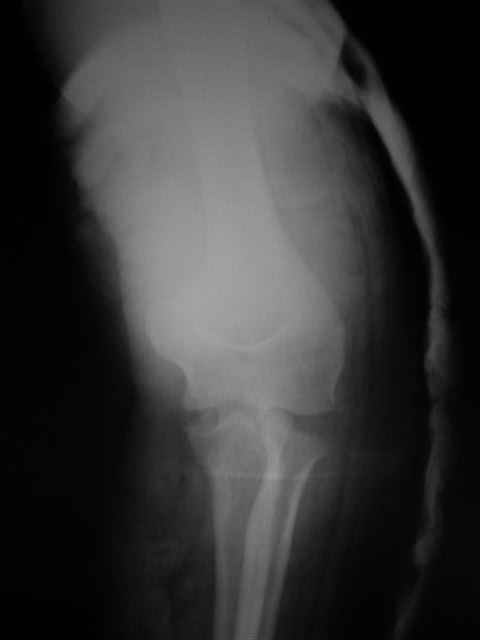

Re: Вывих костей предплечья и перелом головки луче

Вы указали последствия резекции головки луча: нестабильность, вальгусная деформация, влияние на дистальное радиоульнарное сочленение, поэтому при изолированных или сочетанных повреждениях гоовки, стараюсь ее *собрать*, фиксируя межфрагментарными 1,5 - 2,0 мм винтами, по ситуации + L-пластиной. Отмечается ограничение амплитуды ронации-супинации впоследствии, но локтевой сустав остается стабильным. Результаты протезирования головки флотирущими имплантами функционально удовлетворительны и применительны к случаям, когда *собрать* мнооскольчатый перелом невозможно.